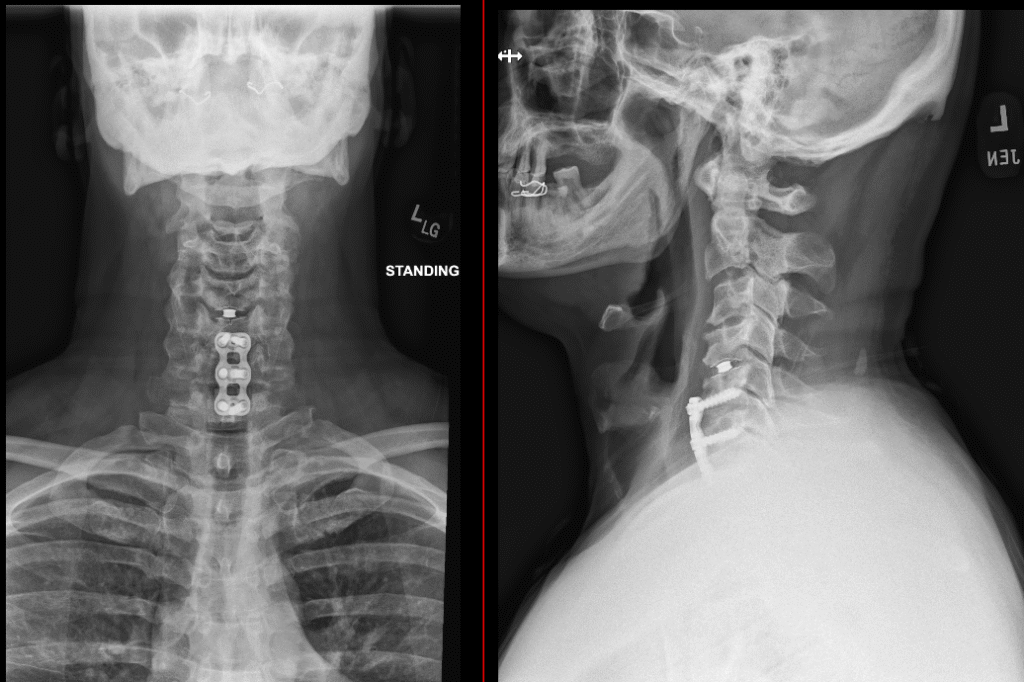

two levels acdf

ACDF C4 7 1024x413